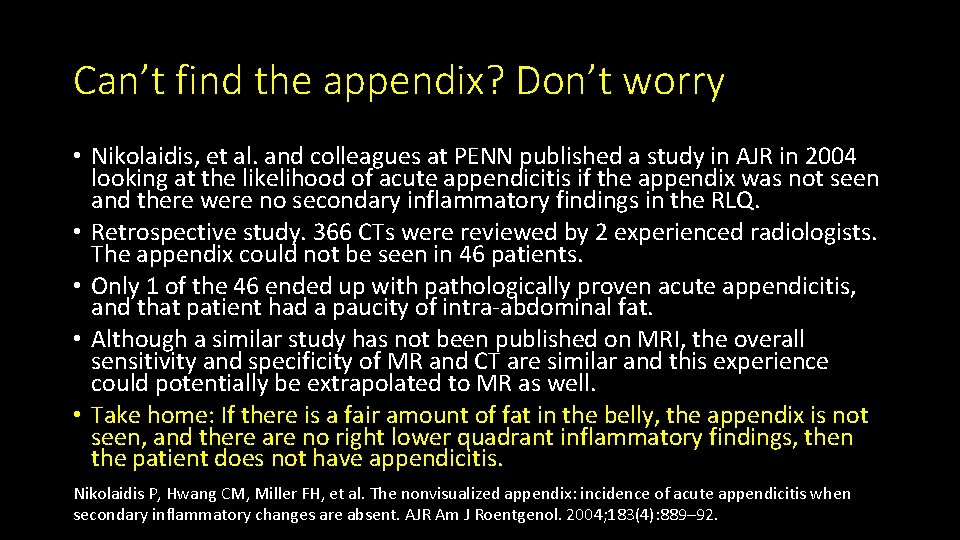

Can’t find the appendix? Don’t worry • Nikolaidis, et al. and colleagues at PENN published a study in AJR in 2004 looking at the likelihood of acute appendicitis if the appendix was not seen and there were no secondary inflammatory findings in the RLQ. • Retrospective study. 366 CTs were reviewed by 2 experienced radiologists. The appendix could not be seen in 46 patients. • Only 1 of the 46 ended up with pathologically proven acute appendicitis, and that patient had a paucity of intra-abdominal fat. • Although a similar study has not been published on MRI, the overall sensitivity and specificity of MR and CT are similar and this experience could potentially be extrapolated to MR as well. • Take home: If there is a fair amount of fat in the belly, the appendix is not seen, and there are no right lower quadrant inflammatory findings, then the patient does not have appendicitis. Nikolaidis P, Hwang CM, Miller FH, et al. The nonvisualized appendix: incidence of acute appendicitis when secondary inflammatory changes are absent. AJR Am J Roentgenol. 2004; 183(4): 889– 92.